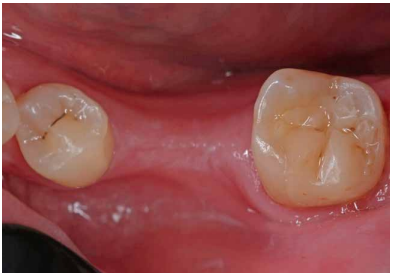

Se realizaron revisiones a 1 mes, 6 y 18 meses (Figuras 9 y 10), observando en la última radiografía de control mejoría en la lesión apical de la raíz distal. En todas las revisiones, la paciente se encontraba asintomática, la prueba de sensibilidad al frío fue fisiológica, al igual que la prueba de palpación, percusión y de mordida. El sondaje y la movilidad continuaban fisiológicos.